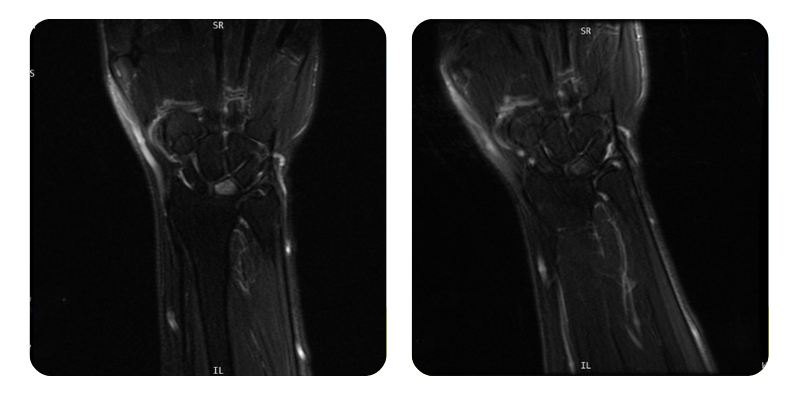

Előtte

Utána

B.A.A., 54 éves – Avaszkuláris oszteonekrózis a bal félholdcsontban

Eredmények: Kéz MRI.

Diagnózis: Avaszkuláris oszteonekrózis a bal félholdcsontban, magas vérnyomás, pajzsmirigy-alulműködés.

Terápiás beavatkozások: 20 alkalom hiperbár oxigénterápia.

Lefolyás: A 20 hiperbár kezelés után a páciens állapota körülbelül 80%-os javulást mutatott, a bal kéz fájdalmai teljesen megszűntek. Funkcionális korlátozás nem észlelhető, a páciens panaszmentesen folytatta mindennapi tevékenységét.